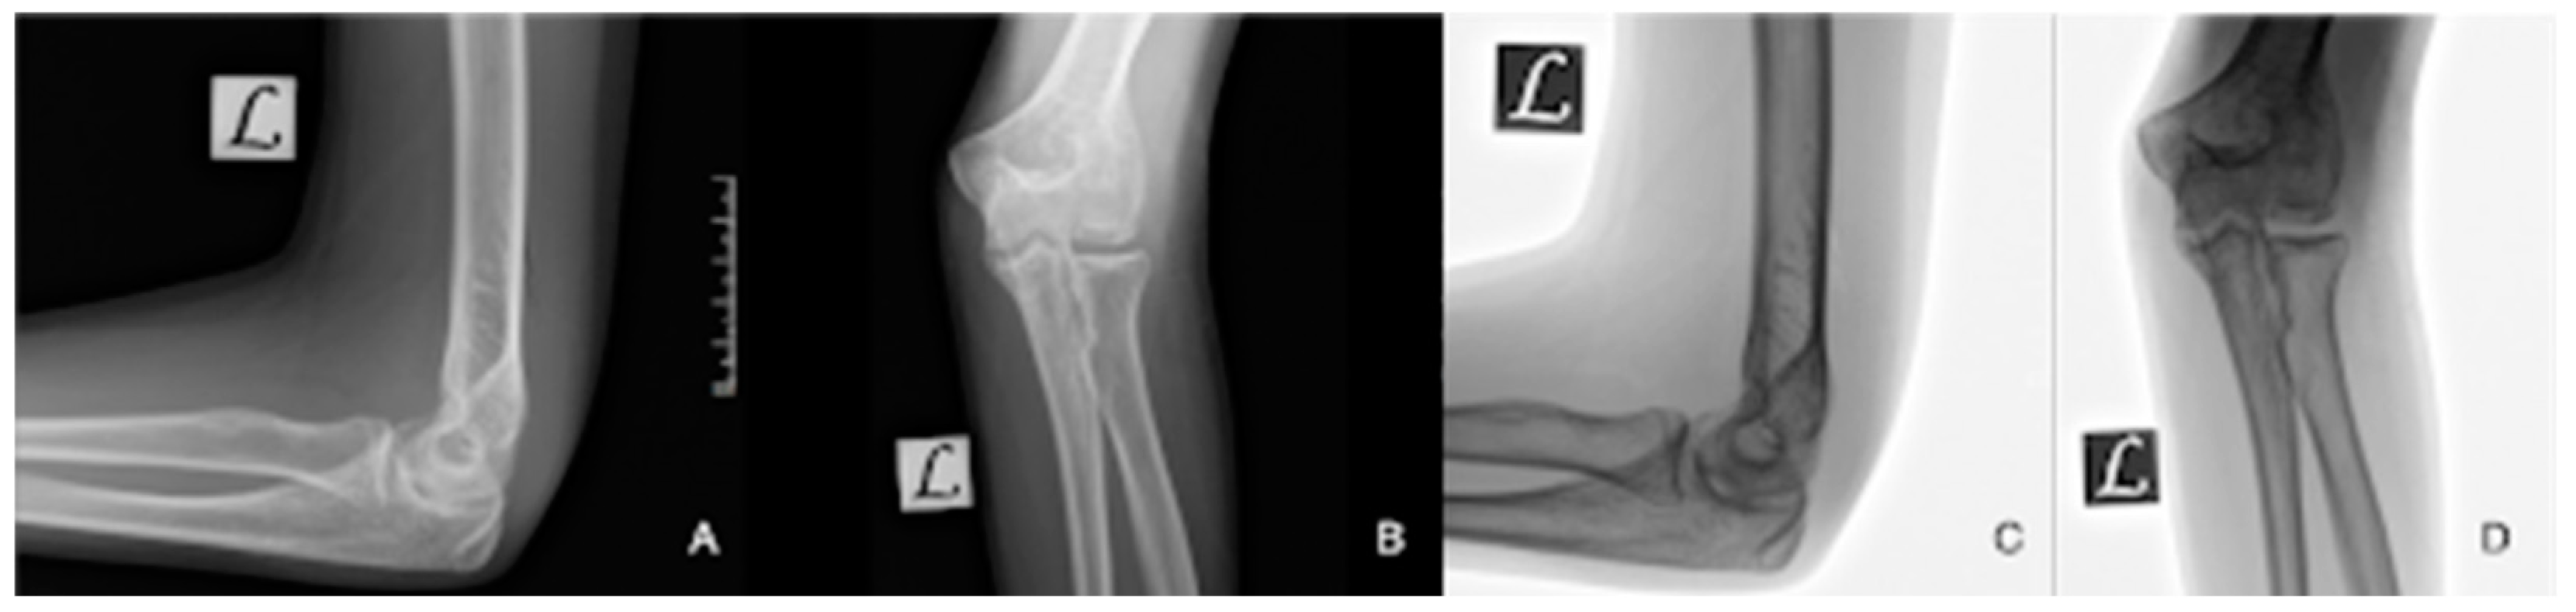

| Stage 1 | Small subchondral compression | Intact Lesion | A stable lesion of the softened area covered by intact cartilage | Thickening of articular cartilage and low signal changes | Small change in signal, without clear fragment margins | Epiphyseal cartilage lesion with necrotic center |

| Stage 2 | Partially detached osteochondral fragment | A lesion with signs of early separation | Lesions with partial discontinuity which are stable when probed | Articular cartilage is breached, with a low signal rim behind the fragment indicating fibrous attachment | Osteochondral fragment with clear margins, without fluid in between | Epiphyseal cartilage lesion with complete or incomplete rim calcification |

| Stage 3 | Completely detached, non-displaced | Partially detached lesion | Lesions with complete discontinuity which are not dislocated (Dead in situ) | High signal changes behind the fragment indicate synovial fluid between the fragment and the underlying subchondral bone | Fluid is partially visible between the fragment and bone | Partially or completely ossified lesion |

| Stage 4 | Completely detached and displaced—loose body | Craters with loose bodies (salvageable or non-salvageable) | Empty defect bed with loose or dislocated fragment | Loose body | Fluid surrounds the fragment but it is still in situ | Healed osseous lesion with scar |

| Stage 5 | Scranton and McDermott modification: Subchondral Cyst | - | - | - | The fragment is completely detached and displaced | Unhealed, detached osseous lesion (Sequestrum) |